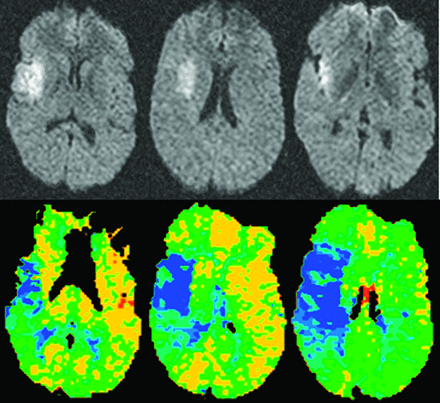

灌注CT是第二个成像模式被用来确定一个近似的半影急性缺血性中风患者。灌注CT图像上获得超快的CT扫描仪通过快速重复扫描后注入碘化对比材料。与一个信号冲刷bolus-contrast灌注CT扫描生成的曲线,可以生成cb v半定量的cb v和地图都未都未。26cb v随着缺血变得更严重,崩溃,都未与灌注CT缺血性核心被确定为一个地区与cb v明显下降。都未CBF和MTT地图展示缺血灌注值低于一个阈值定义为异常的地区的大脑区域。缺血半影操作上定义为该地区的CBF cb v或MTT异常值高于都未崩溃的阈值(图2)。27,28使用灌注CT是目前受到几个因素,与DWI-PWI相比。这些因素是有限的报道缺血性脑(只有2 - 4片对于大多数扫描仪,尽管整个大脑覆盖率现在可以在更新模型),更可靠地确定阈值识别CBF cb v / MTT和异常,都未和小动物成像技术建模工作。灌注CT的一个主要优点是更广泛的可用性和访问与MRI相比。样本大小适度的做的一项研究证明类似目标的识别病人的治疗决定3 -见到时间窗与灌注CT与DWI-PWI相比,但这一发现需要确认更多的患者在多个网站。29日当一些与灌注CT解决当前的问题和可比性DWI-PWI界限不明的近似被证实,实际问题表明,它将成为最常用的成像工具界限不明的近似。

的精确定义预警指示器异常需要进一步验证,但T马克斯延迟超过目前使用2秒可能会需要更精确的描述hypoperfused组织梗死。不匹配的比例大于20%显然需要确定一个研究人群最有可能对治疗作出回应。成像和临床包含/排除标准需要协调确保基线中风的严重程度患者随机不太温和,从而排除高速率在安慰剂组好的结果。除了使用reperfusion-based临床试验DWI-PWI失配的方法,这种方法可用于未来神经保护试验提高招聘更容易应对治疗的患者,特别是在延迟时间点。40目前,灌注CT先进的界限不明的识别是不如mri界限不明的识别。然而,cb v的阈值和CBF需要都未识别核心和hypoperfused地区缺血性梗塞的风险成为更好的特征和组织成像的范围扩大,灌注CT将演变为界限不明的更广泛应用模式识别在临床试验和实践。